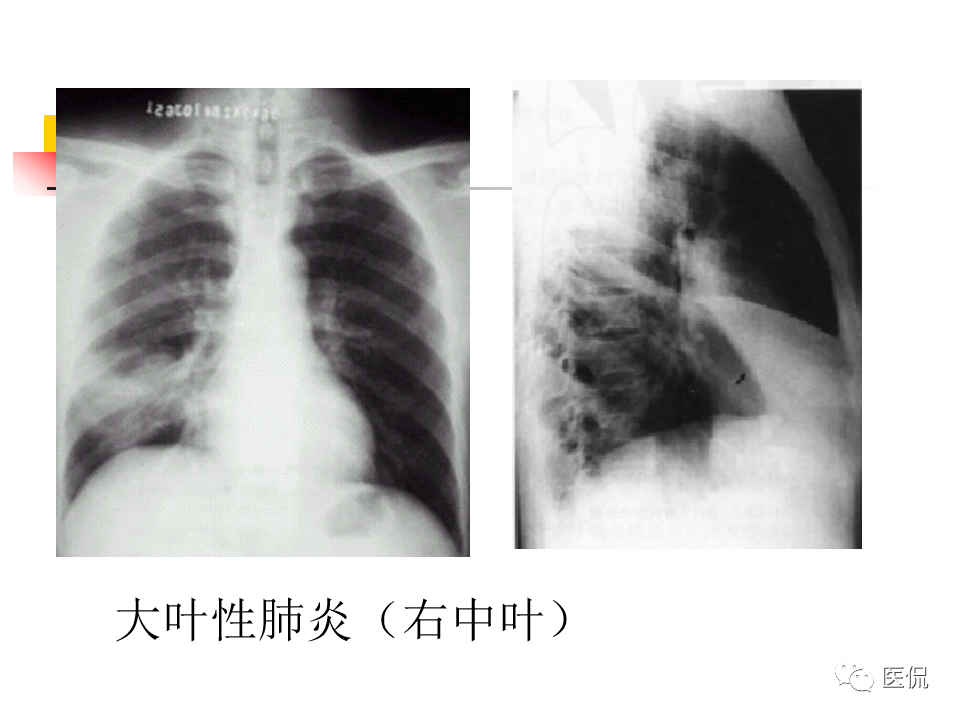

大叶性肺炎|大叶性肺炎的影像诊断

大叶性肺炎影像诊断